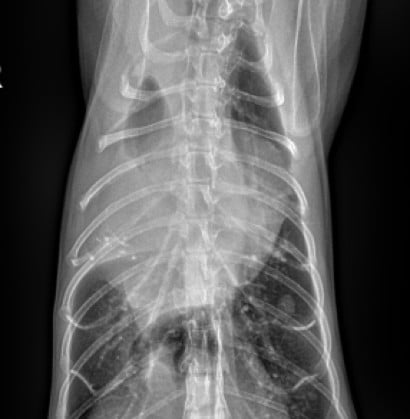

심장질환으로 인한 급성호흡곤란, 폐수종, 쇼크 등 응급 상황에 신속하고 체계적으로 대응합니다. 환자의 증상과 상태에 따라 맞춤형 응급처치 프로토콜이 즉시 적용됩니다.

심비대, 폐수종, 심부전까지 유발할 수 있는 질환.